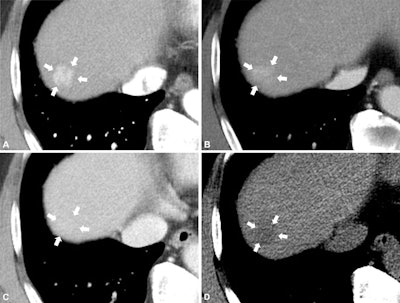

Axial CT images in a 67-year-old man with hepatitis B virus infection–related liver cirrhosis show a 1.8-cm hepatic observation in segment VIII (arrows). The lesion shows (A) nonrim arterial phase hyperenhancement without nonperipheral washout and it remains (B) mildly hyperenhancing in the portal venous phase and shows (C) isoattenuation in the delayed phase. No ancillary features are visible, and the lesion is categorized as LR-3 according to Liver Imaging Reporting and Data System, or LI-RADS, version 2018. (D) On the precontrast image, the lesion appeared as a low attenuating lesion and was upgraded to LR-4 based on precontrast low attenuation as an ancillary feature favoring malignancy. Pathologic examination after hepatic resection served to confirm hepatocellular carcinoma. Images and caption courtesy of the RSNA.Axial CT images in a 67-year-old man with hepatitis B virus infection–related liver cirrhosis show a 1.8-cm hepatic observation in segment VIII (arrows). The lesion shows (A) nonrim arterial phase hyperenhancement without nonperipheral washout and it remains (B) mildly hyperenhancing in the portal venous phase and shows (C) isoattenuation in the delayed phase. No ancillary features are visible, and the lesion is categorized as LR-3 according to Liver Imaging Reporting and Data System, or LI-RADS, version 2018. (D) On the precontrast image, the lesion appeared as a low attenuating lesion and was upgraded to LR-4 based on precontrast low attenuation as an ancillary feature favoring malignancy. Pathologic examination after hepatic resection served to confirm hepatocellular carcinoma. Images and caption courtesy of the RSNA.